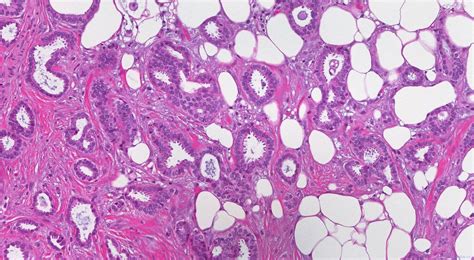

Alright, so what exactly is invasive right breast carcinoma ? Basically, it’s cancer that starts in the right breast and has spread beyond the ducts or lobules where it originated. It’s considered “invasive” because it has broken through the boundaries of the tissue where it began, potentially spreading to other parts of the body. There are various types, with the most common being invasive ductal carcinoma and invasive lobular carcinoma . The former starts in the milk ducts, while the latter begins in the milk-producing lobules. Understanding the type helps doctors determine the best course of treatment. The right breast is simply the location where this process is taking place. This localization is important, as it helps determine the extent of the cancer and guide treatment decisions, like surgery, radiation, and medication. The term “carcinoma” itself refers to a cancer that originates in the epithelial cells – the cells that cover the surfaces of the body, including the breast tissue. This means that when we’re talking about invasive right breast carcinoma , we’re referring to a very specific type of cancer that must be accurately identified and documented for proper care. Guys, remember that early detection is key, and regular screenings are super important. If you feel anything unusual, don’t hesitate to see a doctor! It’s better to be safe than sorry, right?

This kind of cancer isn’t just a single disease; it’s a complex group of conditions, each with its own characteristics and behaviors. Some might grow rapidly, while others may spread to other parts of the body, which is called metastasis. The specific characteristics of the cancer, such as its size, grade, and the presence or absence of certain receptors (like estrogen or HER2), all influence how the cancer is treated and the patient’s prognosis. The journey through this diagnosis can be a tough one, so it’s super important to have a strong support system, including family, friends, and healthcare professionals. Each detail matters when it comes to treatment.